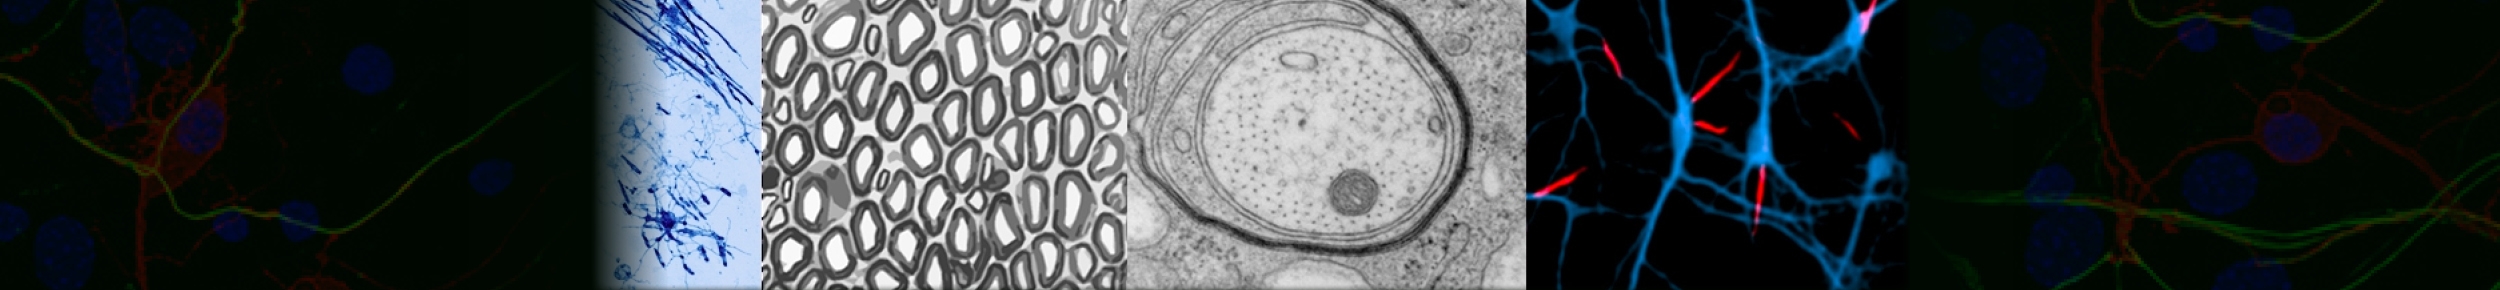

p53 inactivation drives breast cancer metastasis to the brain through SCD1 upregulation and increased fatty acid metabolism

Laue K., Pozzi S., Zerbib J., Bertolio R., Eliezer Y., Cohen-Sharir Y., Winkler T., Caputo M., Ricci A. A., Adler L., Khoury R., Longobardi G., Slutsky R., Leikin-Frenkel A. I., Ovadia S., Lange K., Rustighi A., Piazza S., Sacconi A., Magesh R. Y., Keller F. N., Berthelet J., Schaffer A., Saad R., Israeli Dangoor S., Szczepanowska K., Barshack I., Liao Y., Malitsky S., Brandis A., Broggini T., Czabanka M., Shi W., Merino D., Watson E. V., Blandino G., Erez A., Ashery-Padan R., Medyouf H., Bertero L., Del Sal G., Satchi-Fainaro R. & Ben-David U. (2025), Nature Genetics